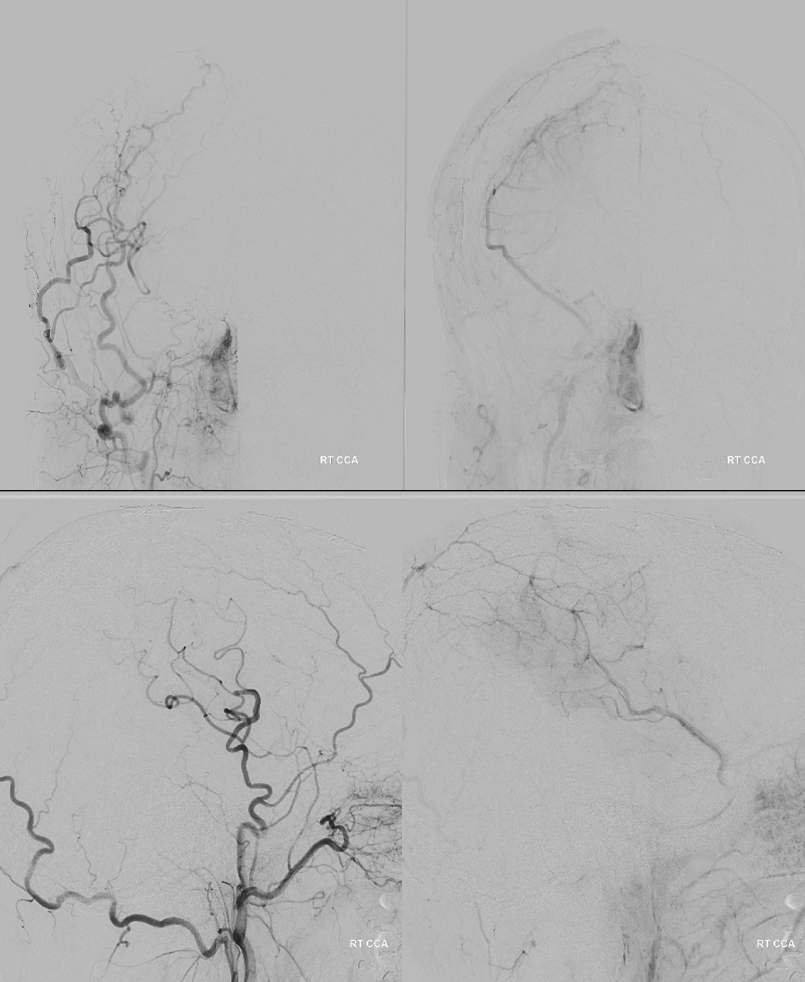

Now we do a BTO of the right A2. Its not a perfect occlusion there is a small endoleak. Still, the brisk filling of right A2 suggests what?

The first SVB is deployed. However, there is a concern. What is it? Look at the measurements of the SVB and the landing zones

The answer is possible endoleak. The distal landing zone may be too short for a nitinol device. The diameter of the proximal SVB is smaller than the expected diameter of the A2 target. Its a critical point. If this is missed, the treatment may fail

The answer is to either balloon it or put in another device. We put in another SBV, now extending it into one of the A2 branches. Yes, one can argue that with working bypass you can just close the A1-A2 junction. Sure. But we did not know this before. And we can always do that later by coiling inside the SVB. Here, we keep options open.

Post SVB 2

Look at the difference in measurements after SBV 2 (top row) and SBV 1 (bottom row). Arrows point to location of the SVB 1 distal landing zone